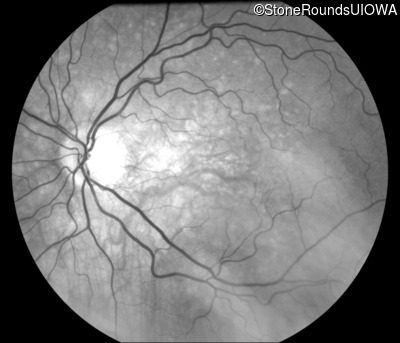

Fluorescein Angiography - Right - 20/20 -3 sc

Exemplar